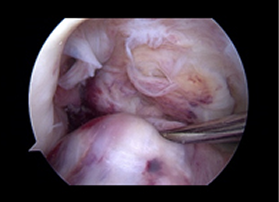

관절내시경 수술 장면

절개가 거의 없어 최소 침습적 수술이 가능하지만, 제한된 공간에서 시행되므로 난이도가 높은 경우가 많아 반드시 숙련된 내시경 전문의에게 시술을 받아야 만족스러운 결과를 얻을 수 있습니다.